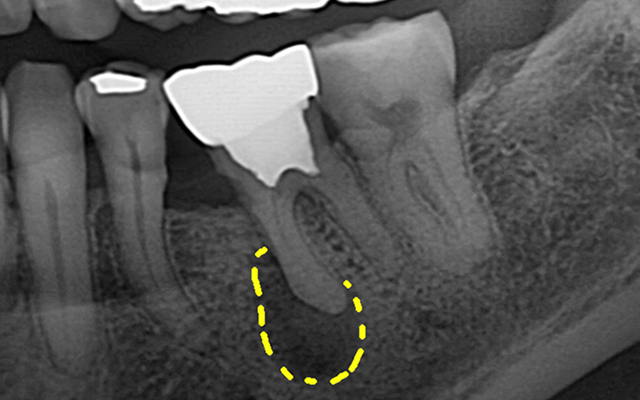

신경치료는 감염되거나 손상된 치수(신경·혈관)를 제거하고

뿌리관 내부를 소독·밀폐하여 치아를 기능적으로 보존하는 치료입니다.

감염 재발을 막기 위해 정밀 진단·무균 술식·밀폐가 핵심입니다.

| 진단·계획 | 치근단 엑스레이 기반 | CT 및 확대 시야 기반의 정밀 진단 |